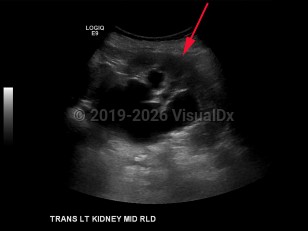

Imaging Studies image of Hydronephrosis - imageId=8359154. Click to open in gallery.  caption: '<span>Transverse grayscale ultrasound image of the left kidney demonstrates moderate to severe hydronephrosis.</span>'

Transverse grayscale ultrasound image of the left kidney demonstrates moderate to severe hydronephrosis.